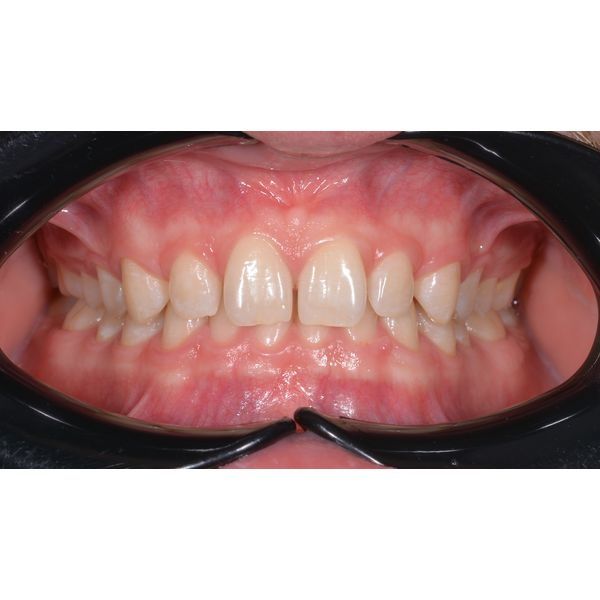

При осмотре наблюдалось:

- глубокое резцовое перекрытие зубов в переднем отделе;

- профицит (избыток) места на верхней челюсти;

- дефицит места на нижней челюсти;

- стираемость зубов.

По результатам диагностики поставили два диагноза:

- глубокий прикус;

- микродентия (уменьшенный размер) зубов верхней челюсти.